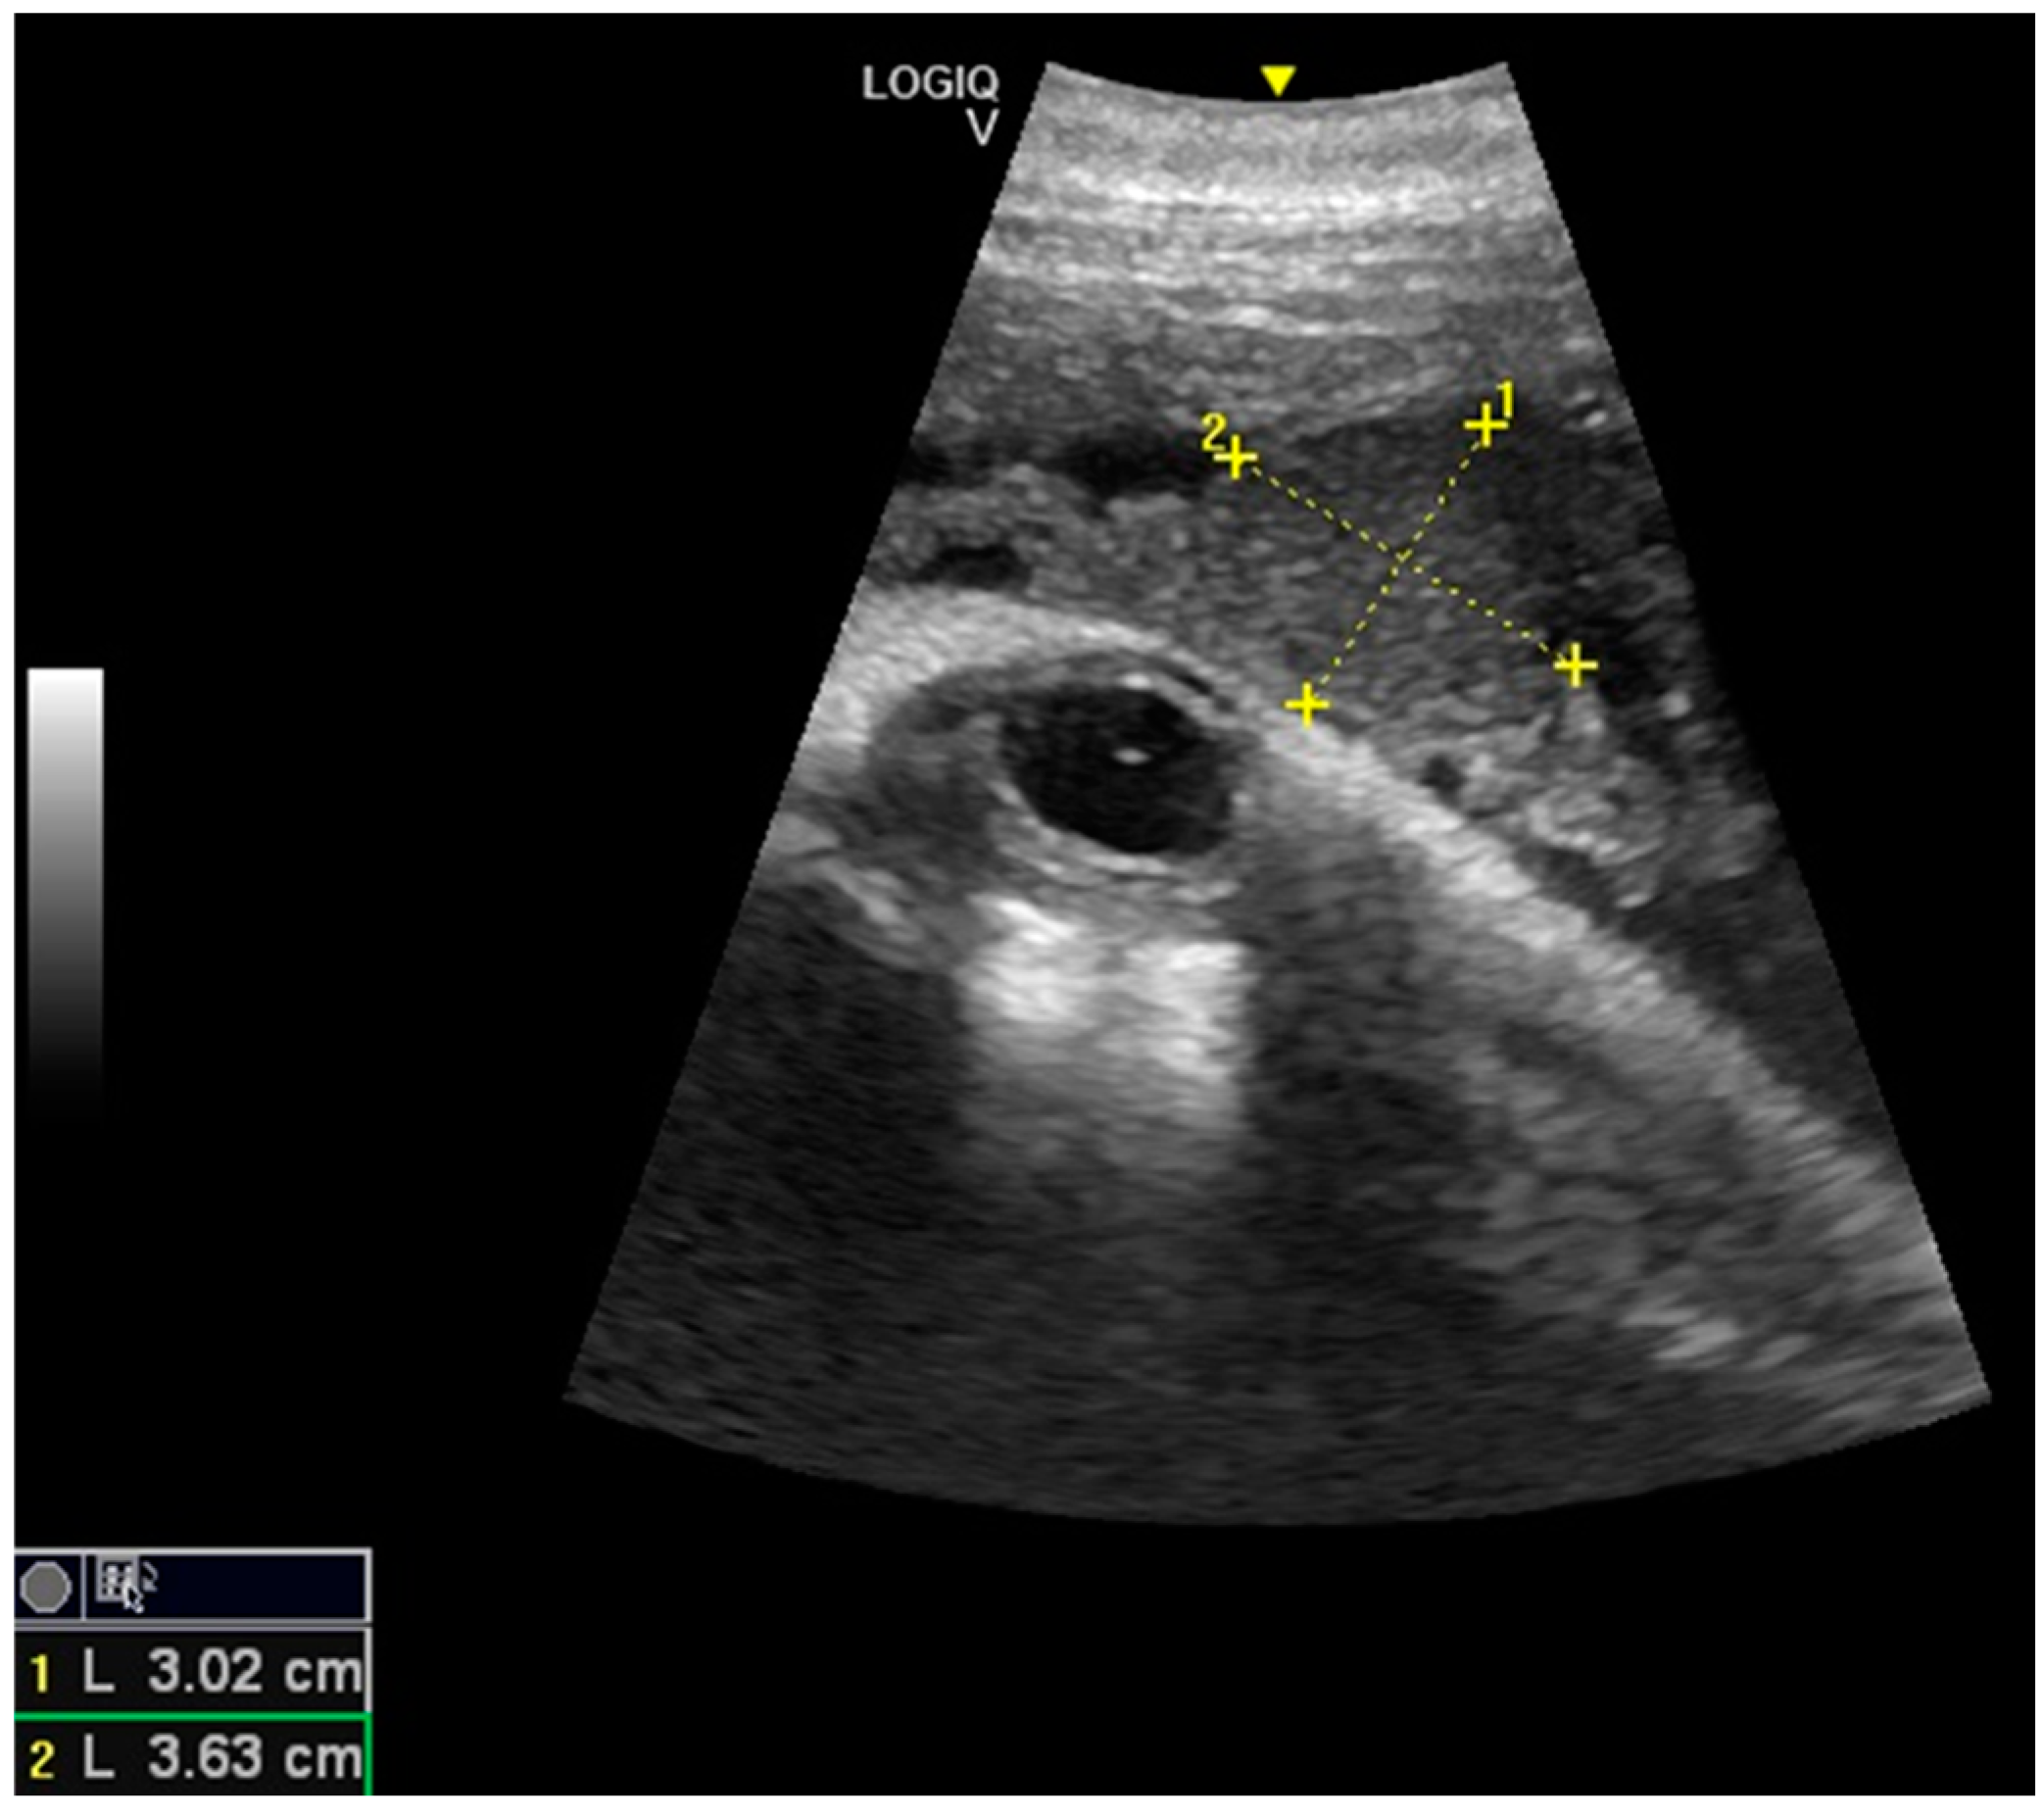

- Ivančič, M.; Gomez, F.M.; Musser, W.B.; Barratclough, A.; Meegan, J.M.; Waitt, S.M.; Llerenas, A.C.; Jensen, E.C.; Smith, C.R. Ultrasonographic findings associated with normal pregnancy and fetal well-being in the bottlenose dolphin (Tursiops truncatus). Vet. Radiol. Ultrasound 2020, 2020, 1–12. [Google Scholar]

- Lacave, G.; Eggermont, M.; Verslycke, T.; Kinoshita, R. Prediction from ultrasonographic measurements of the expected delivery date in two species of bottlenose. Vet. Rec. 2004, 154, 228–233. [Google Scholar] [CrossRef] [PubMed]